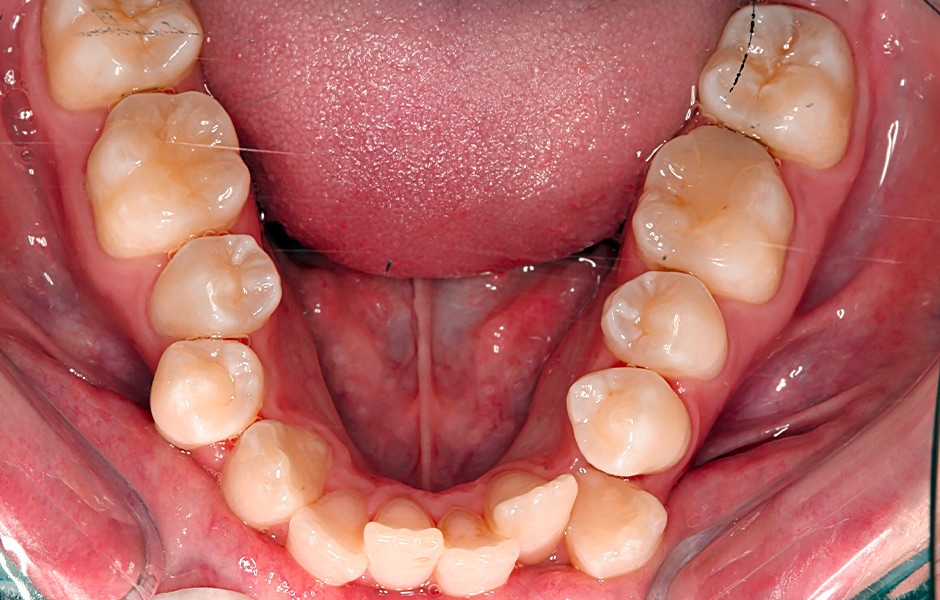

Obr. 1a: Zúžený oblouk – nedostatek místa pro jazyk – blokuje dýchací cesty.

Obr. 1b: Rozšířený oblouk – prostor pro jazyk – uvolňuje dýchací cesty.

Ideálně by měla mít dětská čelist tvar písmene U, nikoli V. Oblouky ve tvaru písmene V vytvářejí vysoké úzké patro, což často způsobuje deviaci nosní přepážky, obstrukci nosních cest dýchacích a podporuje dýchání ústy. Tyto úzké oblouky také vedou k malokluzím, včetně křivých stálých zubů. Když je příliš úzký dolní oblouk, neposkytuje dostatek prostoru pro jazyk (obr. 1a), což často vede k jeho otlačení (70% pravděpodobnost obstrukční spánkové apnoe, OSA). Úzký dolní oblouk nutí jazyk zaujmout polohu vzadu v ústech, což zvyšuje výskyt OSA. Je důležité neextrahovat stálé zuby, protože to může dále zúžit oblouky a způsobit retrakci jazyka, což vede k obstrukci dýchacích cest.